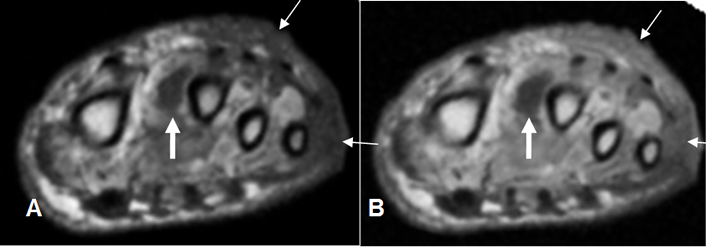

Fig 125 A. Celulitis.

A: RM axial en T1. Ausencia del 5º dedo, por amputación previa. Hay hipointensidad del tejido celular subcutáneo en el dorso y la parte externa del pie, por cambios inflamatorios. (Flechas delgadas).

B: RM axial en T1 con contraste. Existe realce luego de la administración del contraste, lo que indica celulitis. Adicionalmente hay colección líquida entre el 1º y 2º dedos. (Flecha gruesa).